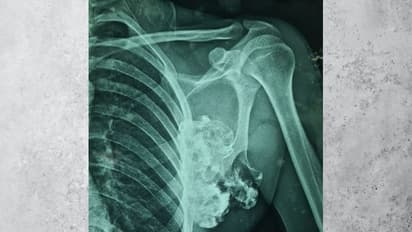

जयपुर. उत्तर भारत के सबसे बड़े सरकारी अस्पताल जयपुर में स्थित s.m.s. अस्पताल में आज एक सफल सर्जरी की गई। दरअसल हनुमानगढ़ जिले से आए एक युवक का जटिल ऑपरेशन s.m.s. अस्पताल के चिकित्सकों की टीम ने किया। इस जटिल ऑपरेशन के लिए 7 से ज्यादा चिकित्सकों की टीम ने अपने अलग-अलग काम की जिम्मेदारी संभाली और कुछ घंटों की सर्जरी के बाद इस जटिल ऑपरेशन को पूरा किया। सर्जरी के बाद चिकित्सकों की टीम ने फूलगोभी के साइज का एक बड़ा ट्यूमर निकाला है। 11 गुना 9 की साइज के इस ट्यूमर को कंधे की स्कैपुला हड्डी से निकाला गया सबसे बड़ा ट्यूमर बताया जा रहा है ।

निजी अस्पताल के चिकित्सकों ने सर्जरी को जानलेवा बताते हुए हाथ नहीं रखा था। उसके बाद युवक का s.m.s. अस्पताल में जांच पड़ताल करने के बाद आज ऑपरेशन किया गया ।s.m.s. अस्पताल के वरिष्ठ आचार्य और विभाग अध्यक्ष डॉ नरेंद्र जोशी ने बताया कि युवक को इस गांठ के कारण कंधे में भारी समस्या का सामना करना पड़ रहा है। उसके कंधे में लेफ्ट साइड में यह ट्यूमर था। यह इतना विशाल था कि छाती की हड्डियों पर भी दबाव बनने लग गया था।

एक्सरे रिपोर्ट देखकर सन्न रह गए डॉक्टर

डॉक्टरों ने जब युवक की एक्सरे जांच कराई तब उसकी हालत देखकर एक बार तो डॉक्टर भी दंग रह गए । बाद में सभी डॉक्टर ने मीटिंग की और इस मीटिंग में ऑपरेशन करने की तैयारी शुरू की गई। ऑपरेशन डॉक्टर जोशी के मार्गदर्शन में डॉक्टर राकेश एवं डॉ विशाल शेखावत की टीम ने किया । डॉक्टर्स की टीम ने बताया कि जो ट्यूमर कंधे की स्कैपुला हड्डी के पास से निकाला गया है । वह दुनिया में प्रकाशित जर्नल्स में स्कैपुला हड्डी की निकाली गई अब तक की सबसे बड़ी ट्यूमर है।